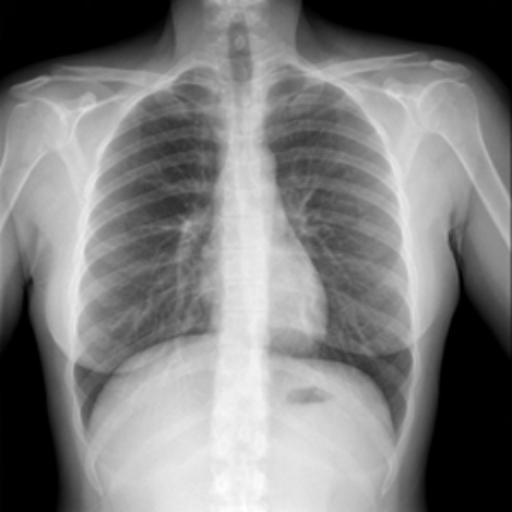

The dataset chosen in this paper is an open-source dataset, the dataset is selected from the open-source database, the database contains 150 lung X-ray images and their corresponding 150 masks, and we select four of them for presentation, the results are shown as follows, the four images in the first row are the original images of the lung X-ray, and the images in the second row in the corresponding position are their corresponding masks, as shown in Fig. 1.

Figure 1. Partial data.